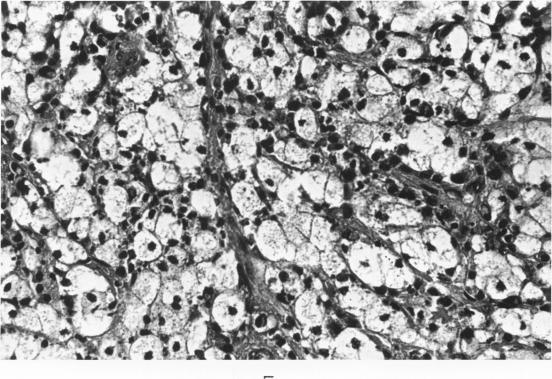

The stages in the development of the Mikulicz cell in human rhinoscleroma were studied in biopsy specimens obtained from 10 patients using light, immunofluorescent and electron microscopy. The Mikulicz cell was identified morphologically as a macrophage, not a plasma cell. Acutely inflamed areas of rhinoscleroma presented abundant bacteria with a slime layer. The microorganism was infrequent and the mucopolysaccharide was scanty in rhinoscleromal tissue, where plasma cells predominated, and in cicatricial fibrous tissue. In the granulomatous stage of rhinoscleroma, the mucopolysaccharide was found within the Mikulicz cells. The vacuoles observed in the Mikulicz cells were considered to be phagosomes containing, principally, bacterial mucopolysaccharide and few bacteria and, to a lesser extent, swollen mitochondria. It was concluded that the slime layer of Klebsiella rhinoscleromatis plays an important role in the pathogenesis of the disease. It is postulated that this material is a nondigestible mucopolysaccharide that resides in the phagosomes of macrophages, increases the osmotic pressure and forms multiple hydropic vacuoles that rupture not only the phagosomes but also the cells, resulting in the liberation of the mucopolysaccharide. This would initiate a cycle that would prolong the disease in the absence of the bacteria.

利用光学显微镜、免疫荧光显微镜和电子显微镜,对10例人鼻硬结病患者活检标本中米库利奇细胞(Mikulicz cell)的发育阶段进行了研究。从形态学上看,米库利奇细胞被确定为巨噬细胞,而非浆细胞。鼻硬结病的急性炎症区域可见大量带有黏液层的细菌。在以浆细胞为主的鼻硬结病组织及瘢痕纤维组织中,微生物较少,黏多糖也很少。在鼻硬结病的肉芽肿阶段,在米库利奇细胞内发现了黏多糖。米库利奇细胞中观察到的空泡被认为是吞噬体,主要含有细菌黏多糖和少量细菌,其次还含有肿胀的线粒体。得出的结论是,鼻硬结克雷伯菌的黏液层在该病的发病机制中起重要作用。据推测,这种物质是一种不可消化的黏多糖,存在于巨噬细胞的吞噬体内,增加渗透压并形成多个水泡样空泡,这些空泡不仅会使吞噬体破裂,还会使细胞破裂,导致黏多糖释放。在没有细菌的情况下,这将引发一个使疾病持续的循环。